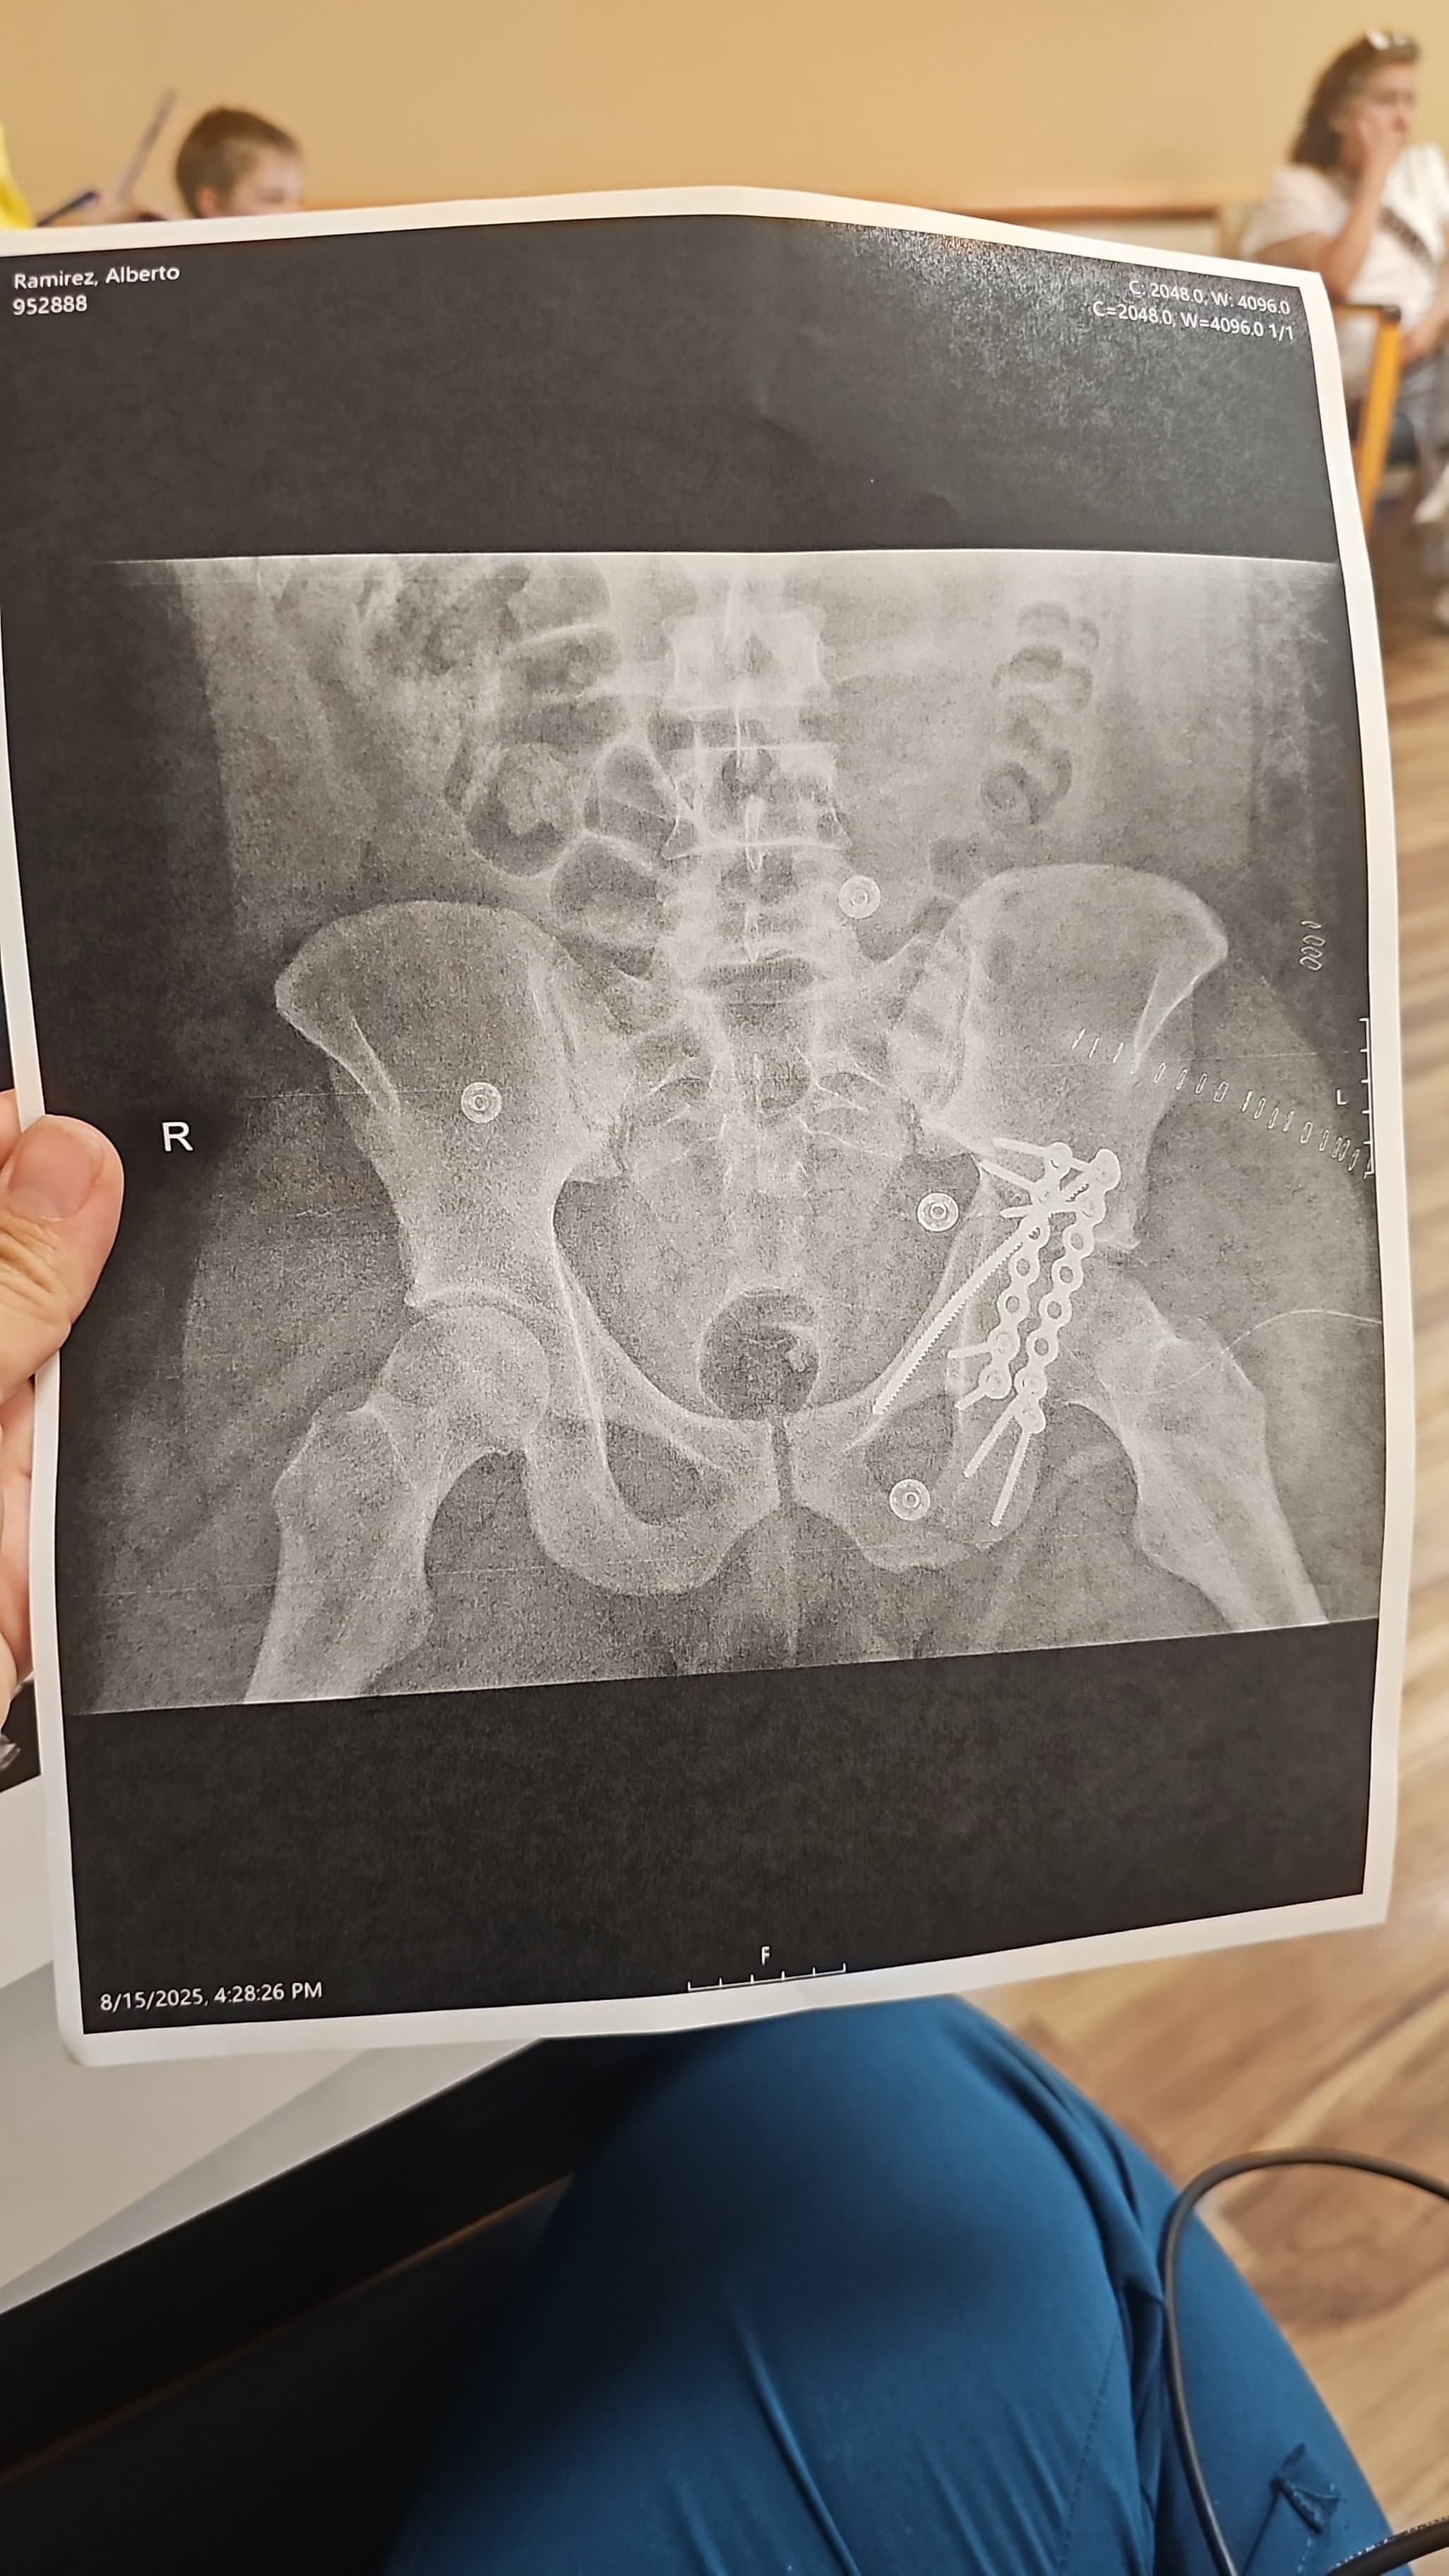

Alberto, my cousin and a beloved member of our family, was recently involved in a serious car accident caused by a drunk driver. The crash left him with a broken arm and a broken hip and severe damage nerve, and he has already undergone two surgeries. Right now, he is just beginning his long recovery journey is going to take him a while to walk and were gonna have to teach him how to walk all over again, and our family is doing everything we can to support him.

Alberto will need several months of physical therapy and specialized care at a rehabilitation hospital to regain his strength and mobility. The costs of medical treatment, therapy, and ongoing care are adding up quickly, and we want to make sure he has everything he needs for the best possible recovery. He lives with us and is a cherished part of our household. This accident has deeply affected all of us, and we are determined to help him get back on his feet.